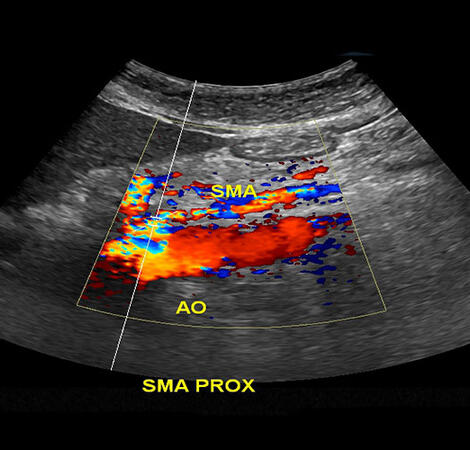

Η στένωση της μεσεντέριου αρτηρίας αναφέρεται στη στενωτική νόσο των αρτηριών που τροφοδοτούν το μεσεντέριο, ένα μεγάλο αγγείο που μεταφέρει το αίμα από την καρδιά προς τα άνω και κάτω άκρα. Η στένωση αυτή συνήθως οφείλεται στην αθηροσκλήρωση, μια κατάσταση όπου οι αρτηρίες συσσωρεύουν αστική ουσία, λίπη, και άλλα υλικά που σχηματίζουν αθηρώματα.

Η αθηροσκλήρωση μπορεί να οδηγήσει σε στένωση των αρτηριών, περιορίζοντας τη ροή του αίματος προς τα όργα που τροφοδοτούν. Στην περίπτωση της μεσεντέριου αρτηρίας, αυτό μπορεί να έχει επιπτώσεις στην καλή παροχή αίματος προς τον εγκέφαλο και τα άνω άκρα. Η σοβαρότητα της κατάστασης εξαρτάται από το βαθμό της στένωσης και τον τρόπο με τον οποίο επηρεάζει τη ροή του αίματος.